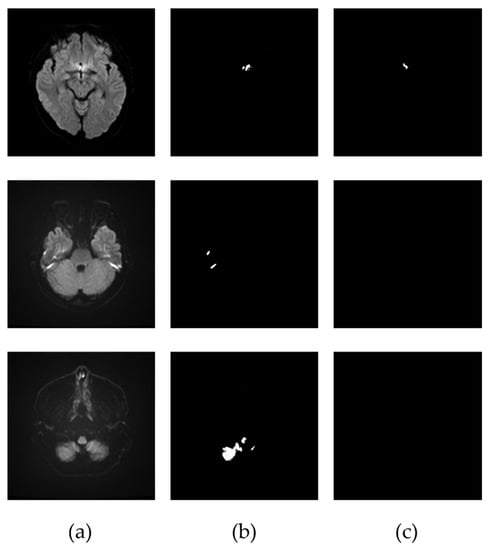

3.2. Extraction of the Infarcted Regions